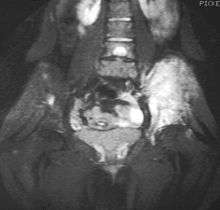

Magnetic resonance imaging (MRI) should be routinely used in the work-up of malignant tumors. It will show the full bony and soft tissue extent and relate the tumor to other nearby anatomic structures (e.g. vessels). Gadolinium contrast is not necessary as it does not give additional information over noncontrast studies, though some current researchers argue that dynamic, contrast-enhanced MRI may help determine the amount of necrosis within the tumor, thus help in determining response to treatment prior to surgery.

Computed axial tomography(CT) can also be used to define the extraosseous extent of the tumor, especially in the skull, spine, ribs, and pelvis. Both CT and MRI can be used to follow response to radiation and/or chemotherapy. Bone scintigraphy can also be used to follow tumor response to therapy.